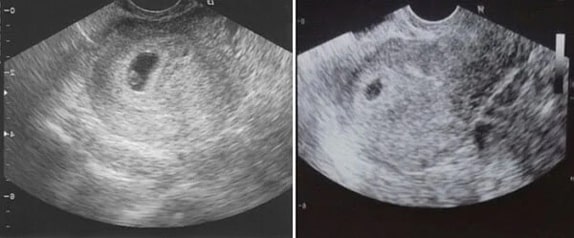

7 Haftalık Gebelik Ultrason Görüntüleri

7 haftalık gebelik bebek boyu: 3 cm

7 haftalık gebelik bebek kilosu: 813 gramdır.

7 Haftalık İkiz Gebelik Ultrason Görüntüleri

8 Haftalık Gebelik Ultrason Görüntüleri

8 haftalık gebelik bebek boyu: 4.6 cm

8 haftalık gebelik bebek kilosu: 1.133 gramdır.

8 Haftalık İkiz Gebelik Ultrason Görüntüleri